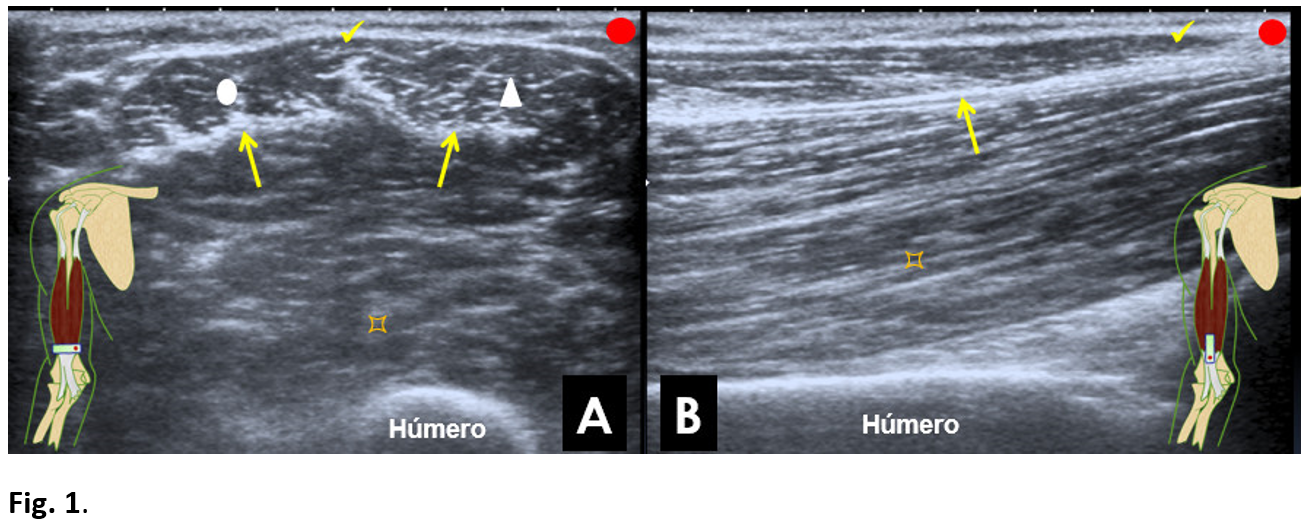

On the ultrasound study, in long axis (Fig. 3A), there was an interruption of the muscular fibrillary pattern and retraction of the central septum of the biceps. The superficial tendinous fibers and the bicipital aponeurosis were intact. In the more superficial segment (Fig. 3B), an echogenic, heterogeneous image of irregular morphology was observed between the bicipital aponeurosis and the muscle fibres of the anterior brachial muscle, which corresponds to fibrous scar. Some retraction of the superficial and deep fibro-fatty bundles and of the medial tendon septum of the biceps could also be appreciated.

Figure 3: Over the most distal portion of the biceps brachii muscle.

Internal longitudinal section. (A) Disruption of the distal fibers of the biceps (white circle). Retraction of the central tendinous septum (arrow). Persistence of fibers corresponding to the bicipital aponeurosis (tick). Anterior brachial muscle (pointed square).

External longitudinal section. The fibrous scar (star). Retraction of the central tendinous septum (arrow). Anterior brachial muscle (pointed square).